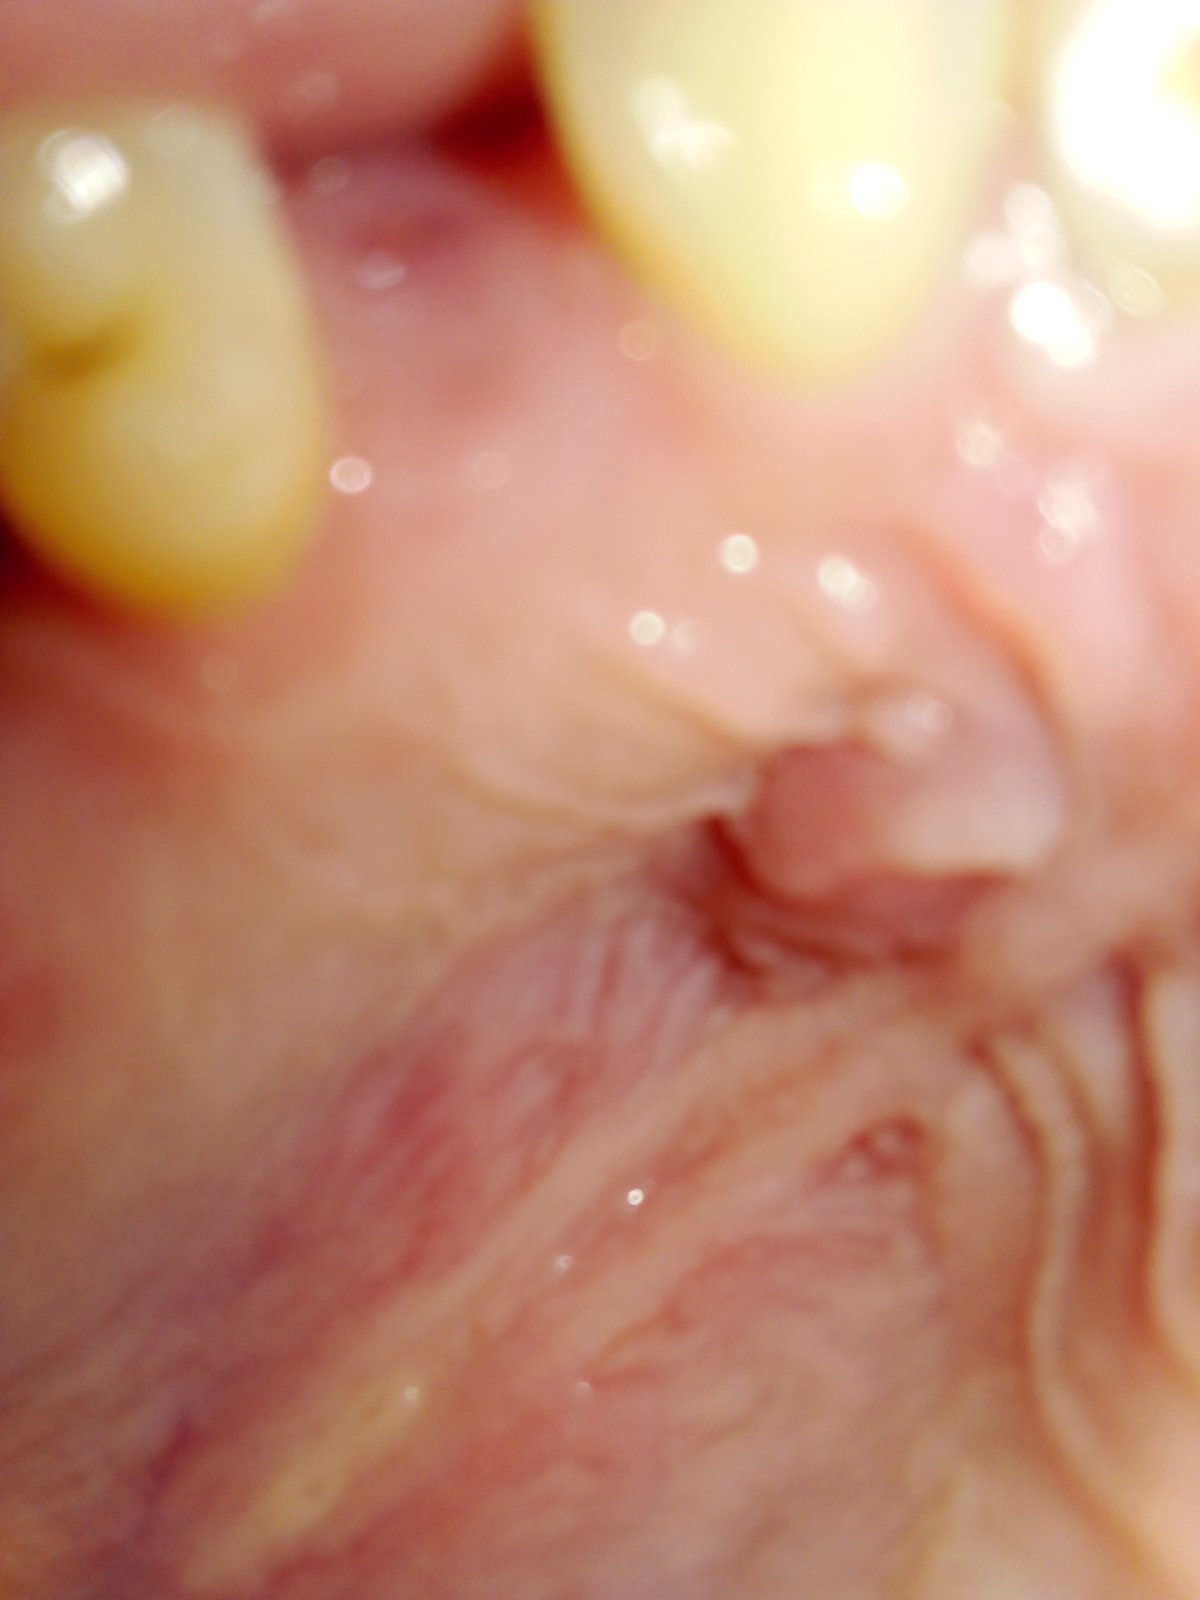

Dobrý deň mám 15 rokov a mám na dasne respektíve na podnebí takú,,hrčku " naposledy ma to aj bolelo, dostala som atb. a nejak to tuším aj prerezali teraz na doyk cítim taký tlak, nebolí to. V piatok by som mala ísť zubarke asi na plnenie kanálikov z minula, neviete čo mi budú robiť ci to zase prerezu?

Ak to neboli q nebude tam hnis už nie.